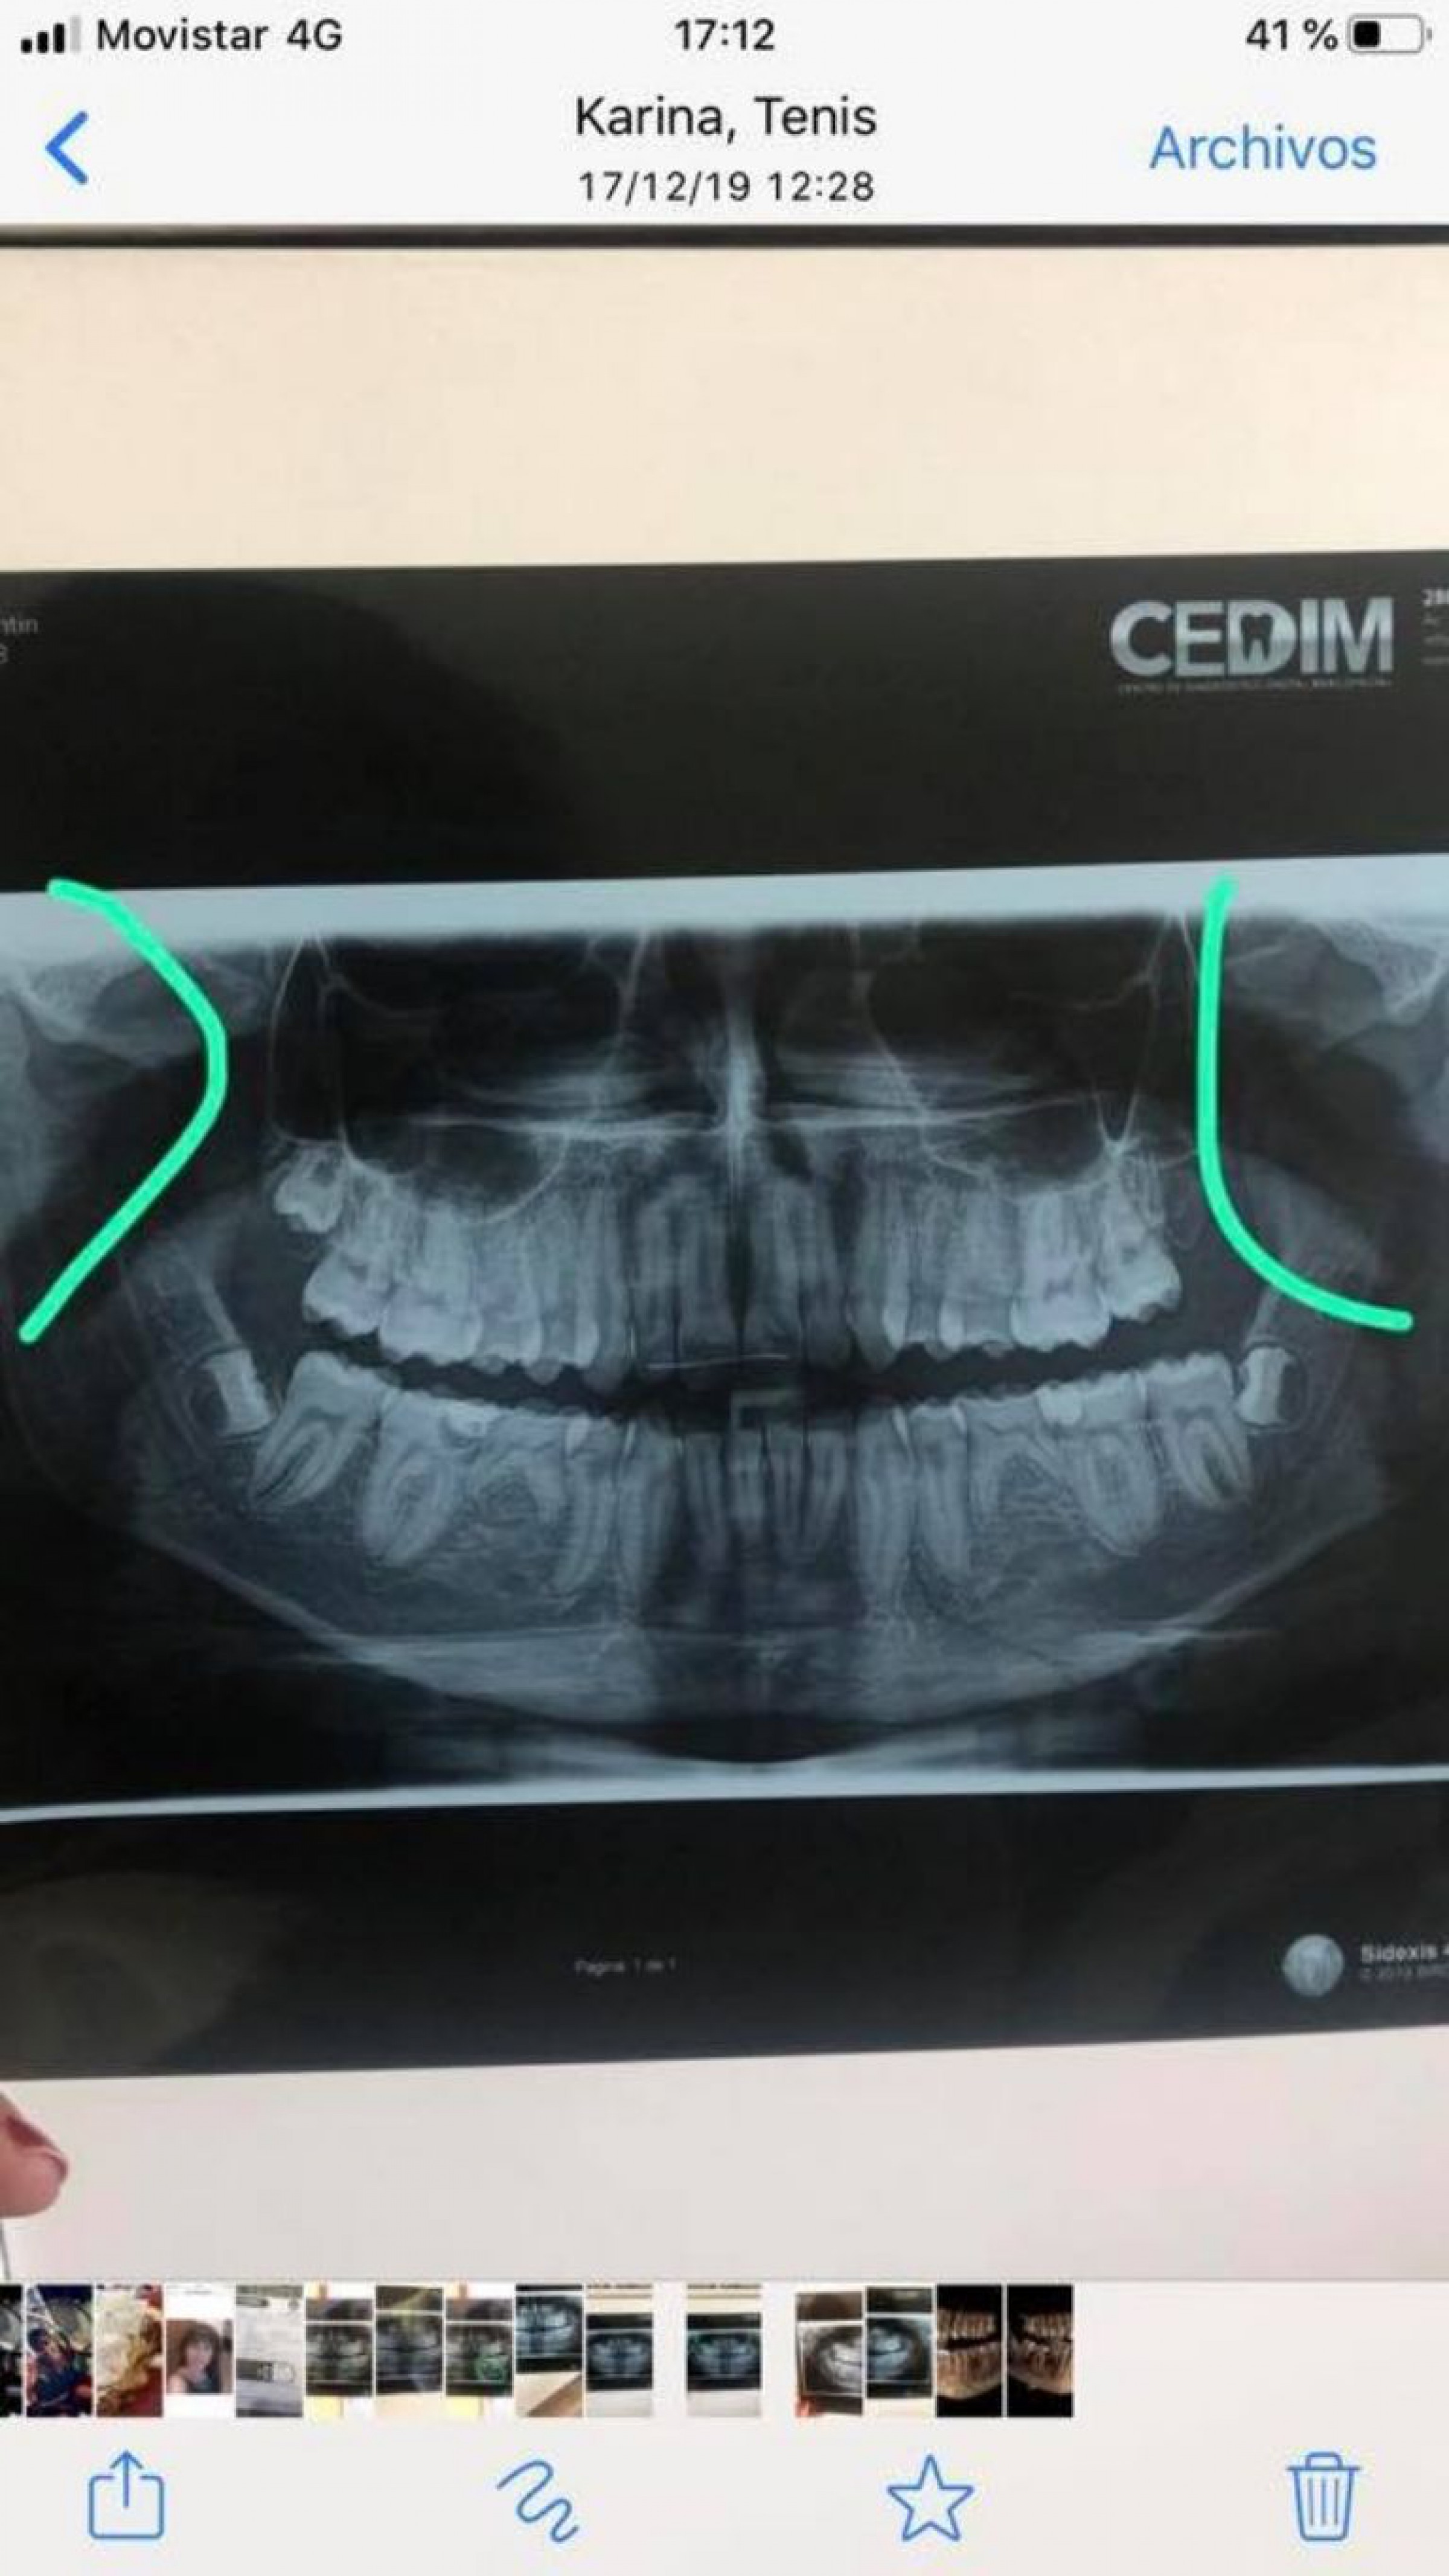

En el mismo denunciaba que a Valentín, su hijo, un jugador de rugby le rompió la mandíbula generando muchas consecuencias y dolencias físicas: ”Basta de violencia! El 14 de diciembre valentin, mi hijo de 16 años fue a un egreso en el club madryn. En un momento desde atras y sin aviso recibe golpes de puño de un violento de 17 años, sin aviso y sin motivo alguno. La golpiza brutal le causo doble quebradura de mandíbula, intervencion, dolor,perdida de 7kg por tener que alimentarse con una sonda, boca bloqueada y lo mas desesperante y traumático: un “ no entender porque le paso esto”. Este individuo le truncó sus planes del verano… entrenar, trabajr y pasarlo bien c sus amigos en la playa , ya que habia rendido sus materias perfectamente para estar libre y disfrutar.esta publicación tiene como unico fin “ informar” a todos los padres y chicos de las cosas que pasan en esta ciudad y de las que la gente prefiere no hablar…. claro…. hasta que les toca vivrlo en carne propia”